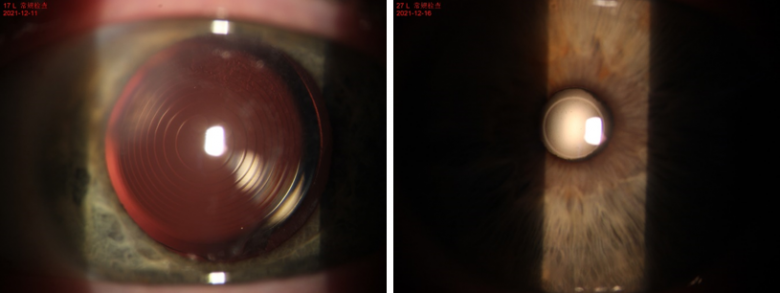

▲手术非常成功,人工晶状体位置居中

▲术前(左)术后(右)对比图,白内障已成功摘除